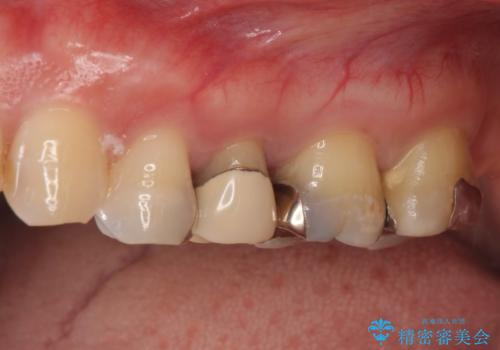

- 左上の奥歯を綺麗にしたいといらっしゃった方の症例です。

左上4、5、6、7番目の歯をオールセラミッククラウンにより補綴しました。